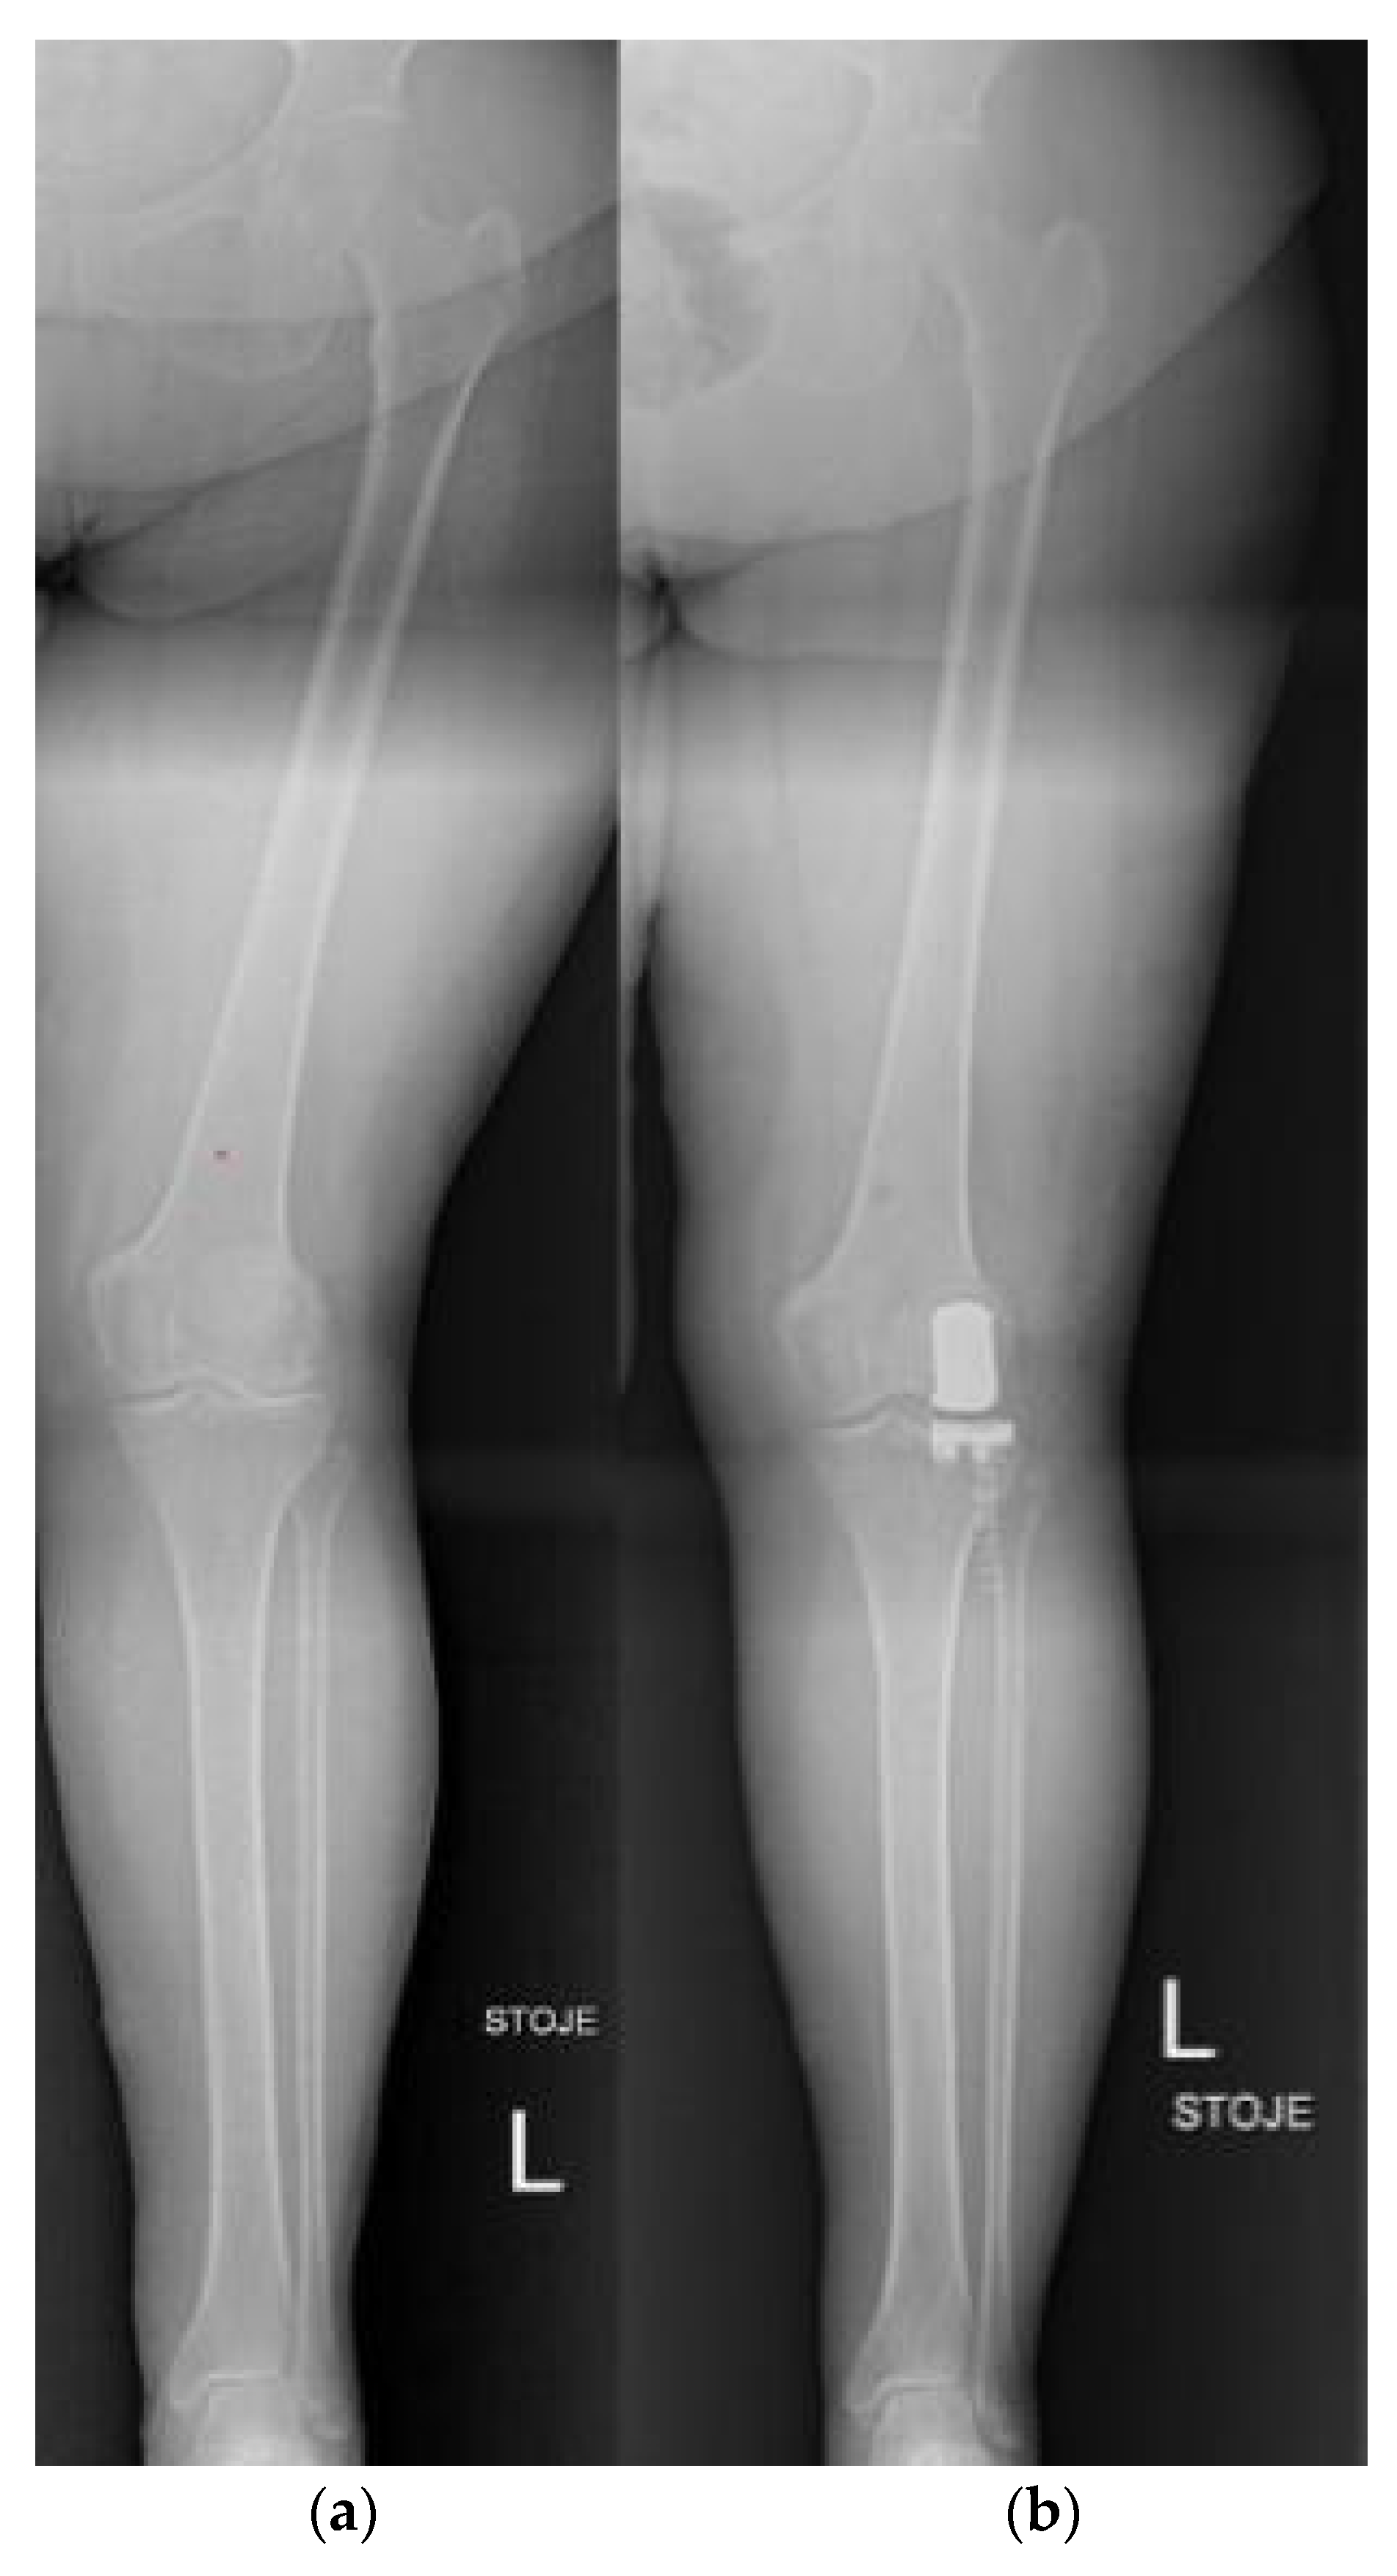

3.6. Knee

5.6. Knee